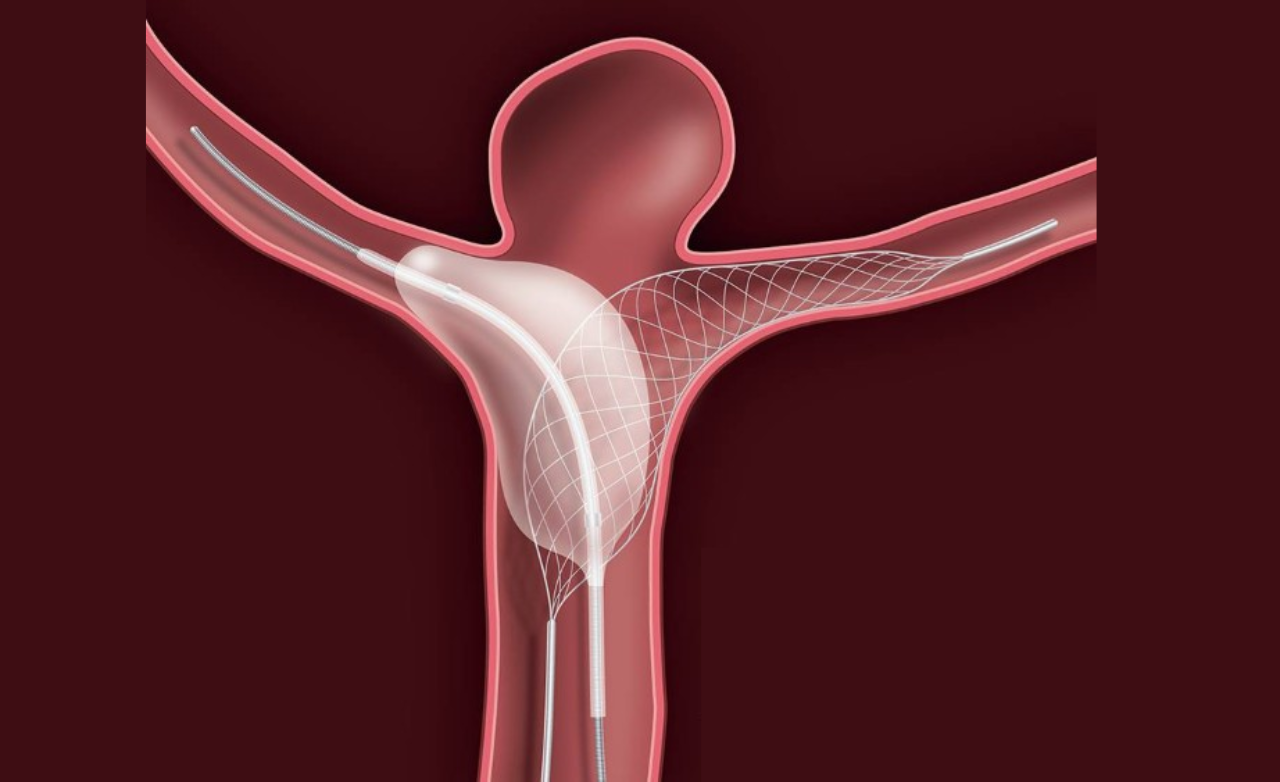

Flow diverter treatment is a minimally invasive procedure used to treat complex brain aneurysms that are difficult to manage with surgery or coiling. It is commonly recommended for wide-neck or hard-to-reach aneurysms.

A special device is placed inside the parent artery to redirect blood flow away from the aneurysm, allowing it to heal naturally while maintaining normal brain circulation.